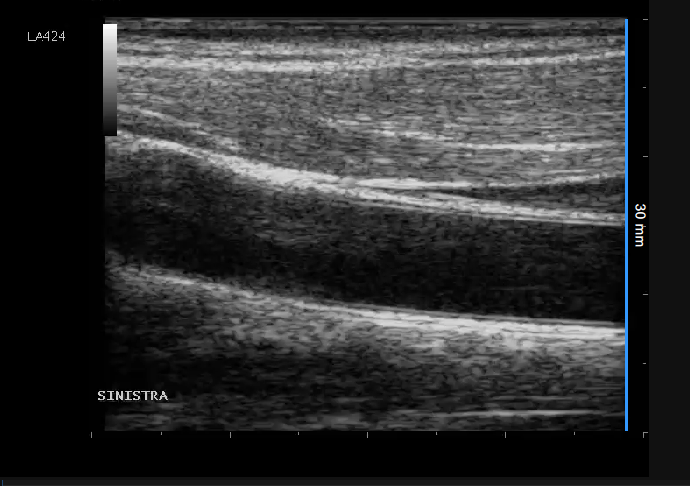

- Locate, in ultrasound image, a range of known distance (30 mm. in the example of figure).

- In the B-mode setup panel, select from the drop-down menu, the distance specified above.

- In the B-mode setup panel, click on the Set B-Mode Calibration button (button remains active).

- Draw a line on the image corresponding to the known distance: click on one end and drag the mouse to the other extreme (press the Shift key or CTRL Shift keys on your keyboard if you want the line to be not vertical or horizontal).